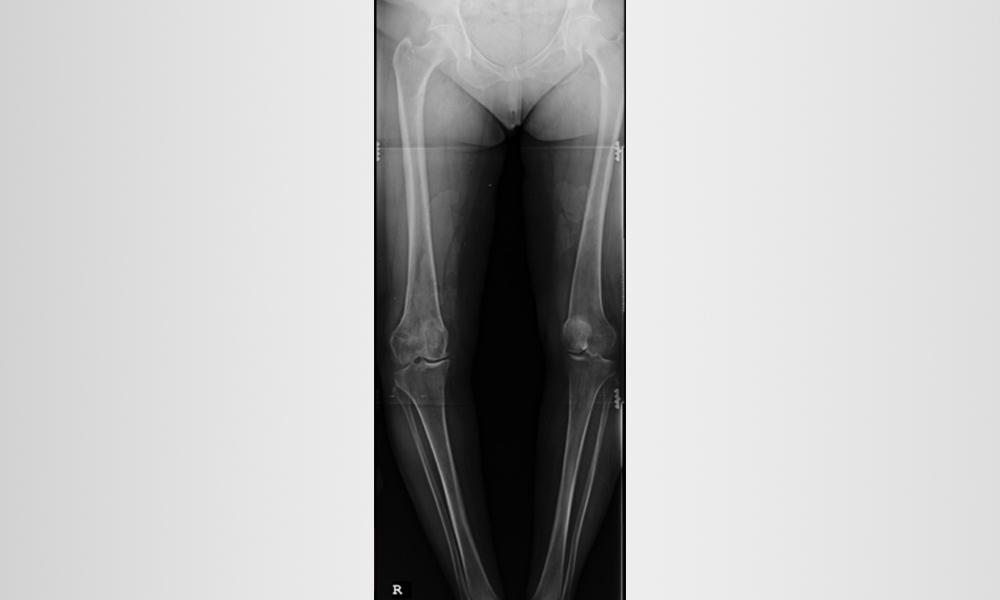

Diz ve bacağınızın kemikleri düzgün hizalanmadığında osteoartrit gelişebilir. Bu, dizinizin iç (medial) veya dış (lateral) tarafına fazladan baskı uygulayabilir. Zamanla bu ekstra basınç, kemikleri koruyan pürüzsüz eklem kıkırdağını aşındırarak dizinizde ağrı ve sertliğe neden olabilir.

X ışınları dizde normal eklem boşluğunu ve dizin bir tarafında osteoartriti gösterir. (Sol) Sağlıklı bir dizin bu röntgeni tibia ve femur arasındaki normal eklem boşluğunu gösteriyor. (Sağ) Bu röntgende, osteoartrit dizin iç kısmına zarar vermiş. Tibia ve femur birbirine sürtünerek ağrıya neden olur.

- Eğri bacak dizilimini düzeltmek için